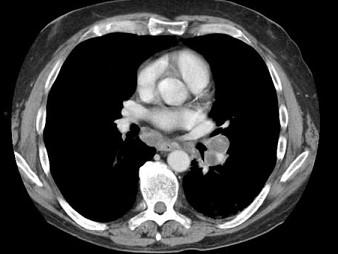

60岁,男,体检胸片发现异常,CT检查如图,请选出最可能的诊断 ( )A、韦格肉芽肿B、支气管腺瘤C、错构瘤D、肺结核E、肺癌

问题 60岁,男,体检胸片发现异常,CT检查如图,请选出最可能的诊断 ( )

选项 A、韦格肉芽肿 B、支气管腺瘤 C、错构瘤 D、肺结核 E、肺癌

答案 E